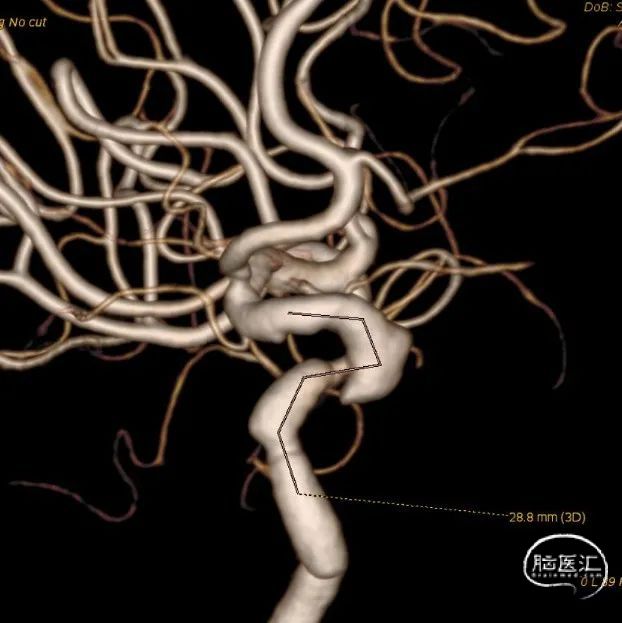

左侧颈内动脉重建(左侧狭窄及扩张较右侧更甚)

1. 患者双侧颈内动脉多发瘤样扩张及狭窄,其中左侧为甚,破裂出血及出现缺血事件风险较高

2. 拟单枚Surpass Streamline覆盖长段病变